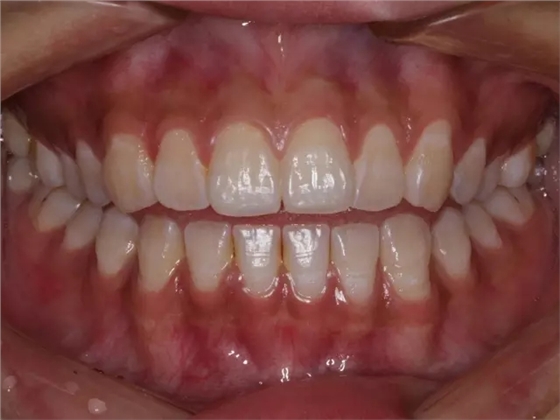

然后,第二磨牙造成咬合干擾、早接觸,前牙開(kāi) 牙合…………